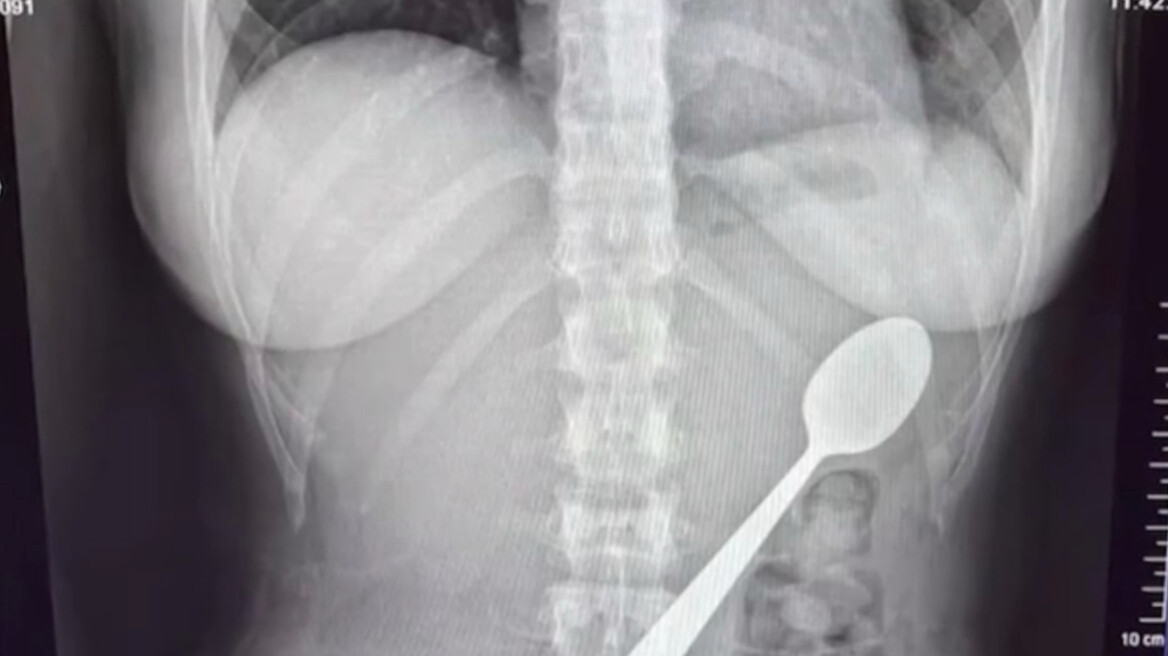

Αρχικά, η Ρέιμι δεν ένιωσε σοβαρή δυσφορία. Όταν ο σύντροφός της επέστρεψε στο σπίτι, δεν του αποκάλυψε το συμβάν. Ωστόσο, μετά το δείπνο, η συνειδητοποίηση της σοβαρότητας της κατάστασης την οδήγησε στο να αναζητήσει ιατρική βοήθεια. Οι εξετάσεις αποκάλυψαν ότι το κουτάλι ήταν πολύ μεγάλο για να αποβληθεί φυσιολογικά, με αποτέλεσμα να αποφασιστεί η αφαίρεσή του μέσω γαστροσκόπησης.

Το διάστημα που ακολούθησε μέχρι την επέμβαση ήταν ιδιαίτερα δύσκολο. Η Ρέιμι περιέγραψε ότι αισθανόταν το κουτάλι να κινείται μέσα στο σώμα της, προκαλώντας φούσκωμα, ναυτία και έντονη δυσφορία. Δύο ημέρες αργότερα, οι γιατροί κατάφεραν να αφαιρέσουν επιτυχώς το κουτάλι με ενδοσκοπική διαδικασία, υπό αναισθησία. Κατά τη διάρκεια της επέμβασης, χρειάστηκε να περιστραφεί το όργανο μέσα στο στομάχι, προκαλώντας μια μικρή γαστρική αιμορραγία, ωστόσο η διαδικασία ολοκληρώθηκε με επιτυχία.